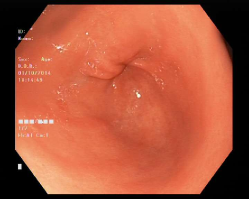

4.1.7 Gastrointestinal endoscopy

Endoscopies are used to detect diseases in the human digestive system. Images from inside the gastrointestinal tract can be used to help doctors detect diseases early. The used dataset 777https://www.kaggle.com/datasets/abdallahwagih/kvasir-dataset-for-classification-and-segmentation contains eight image categories of the digestive system obtained through the endoscopy imaging technique, as shown in Fig. 8. There are a total of 6000600060006000 images that can be used in training and testing machine learning algorithms.

Refer to caption

(a) Normal cecum

(b) Normal pylorus

(c) Normal z-line

(d) Dyed lifted polyps

(e) Dyed resection margins

(f) Esophagitis

(g) Polyps

(h) Ulcerative-colitis

Figure 8: Gastrointestinal endoscopy images.